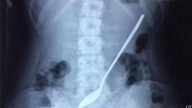

浙江女孩誤吞20公分長鋼杓 3天後才覺不舒服

浙江一名18歲女孩,不小心誤吞一個20公分長的鋼杓,3天後覺得不舒服才去醫院求助,所幸醫生花了兩小時...

驚險!大陸11歲男孩把100克金條吞入腹中

近日,江蘇蘇州11歲男孩小錢(化姓)在家中玩耍時,不慎將一枚重100克的金條吞入腹中。兩天後,經過醫...